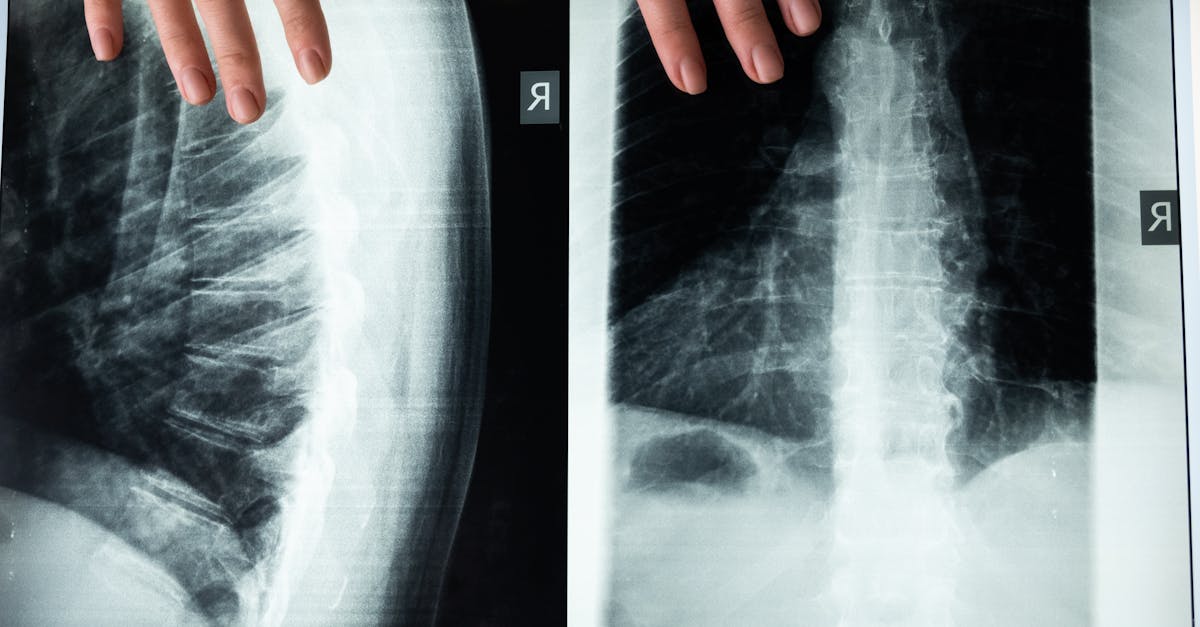

Des examens d’imagerie médicale, tels que des radiographies ou une IRM, sont ensuite nécessaires pour visualiser l’état de la colonne vertébrale et déterminer l’étendue de la sténose. Ces images permettent de diagnostiquer avec précision la condition des espaces au sein de la colonne vertébrale.

Après l’évaluation initiale, des examens d’imagerie médicale sont souvent nécessaires pour confirmer le diagnostic. Les radiographies, IRM (Imagerie par Résonance Magnétique) ou scanners permettent de visualiser la colonne vertébrale et d’identifier les zones rétrécies. Ces examens fournissent des données précieuses pour comprendre l’étendue de la sténose et son impact sur le système nerveux.

- Imagerie médicale : Effectuer une IRM ou des radiographies pour visualiser l’état de la colonne vertébrale.

Étape 3 : Investigations par imagerie

Une fois l’évaluation médicale effectuée, il est souvent nécessaire de recourir à des examens d’imagerie médicale pour confirmer le diagnostic. Les méthodes courantes incluent les radiographies et l’IRM (Imagerie par Résonance Magnétique). Ces examens permettront d’observer la structure de la colonne vertébrale, d’identifier les zones de compression et d’exclure d’autres conditions qui pourraient causer des symptômes similaires.

Importances des radiographies

Les radiographies peuvent révéler des changements dégénératifs dans les vertèbres et les articulations. Toutefois, elles ne fournissent pas une image claire des tissus mous, rendant l’IRM particulièrement utile pour visualiser les disques intervertébraux et les nerfs.

| 3. Imagerie médicale | Réalisation de radiographies ou d’IRM pour visualiser la colonne vertébrale. |

À cette étape, des examens d’imagerie médicale sont généralement requis. Les radiographies peuvent d’abord être effectuées pour observer la structure osseuse de la colonne vertébrale. Toutefois, une IRM (Imagerie par Résonance Magnétique) est souvent nécessaire pour visualiser les tissus mous et confirmer la présence d’une sténose.

Pour affiner le diagnostic, il est souvent nécessaire de recourir à des examens d’imagerie. Les radiographies et les IRM sont deux outils précieux dans cette démarche. Ces examens permettent de visualiser la colonne vertébrale et d’identifier les modifications structurelles, comme un rétrécissement des canaux vertébraux qui pourrait indiquer une sténose spinale. En cas de doute ou si des symptômes persistants émergent, d’autres examens comme la saccoradiculographie peuvent être suggérés pour comprendre le phénomène en jeu dans le canal lombaire.

Les examens d’imagerie médicale, comme les radiographies et les IRM, sont alors réalisés pour confirmer la présence de la sténose. Ces technologies permettent de visualiser la structure interne de la colonne vertébrale et d’identifier la compression des nerfs ou de la moelle épinière. Une saccoradiculographie peut également être utilisée pour évaluer la dynamique du canal lombaire et identifier les zones problématiques plus précisément.